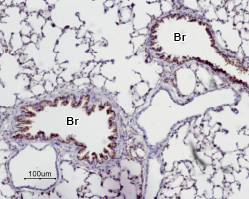

Expression of Adenosine A2A Receptor in mouse diagonal bandImmunohistochemical staining of mouse diagonal band using Anti-Adenosine A2A Receptor Antibody (#AAR-002). A2aR (green) appears in the broca of individual neurons (arrows) and in neuropil (asterisk). DAPI is used as the counterstain. Expression of Adenosine A2A Receptor in rat lungImmunohistochemical staining of paraffin emedded rat lung sections using Anti-Adenosine A2A Receptor Antibody (#AAR-002), (1:50). A2aR is expressed in the respiratory epithelium of the bronchioli (Br). Note that smooth muscle and endothelium in blood vessels are negative. Hematoxilin is used as the counterstain.

Expression of Adenosine A2A Receptor in rat lungImmunohistochemical staining of paraffin emedded rat lung sections using Anti-Adenosine A2A Receptor Antibody (#AAR-002), (1:50). A2aR is expressed in the respiratory epithelium of the bronchioli (Br). Note that smooth muscle and endothelium in blood vessels are negative. Hematoxilin is used as the counterstain.